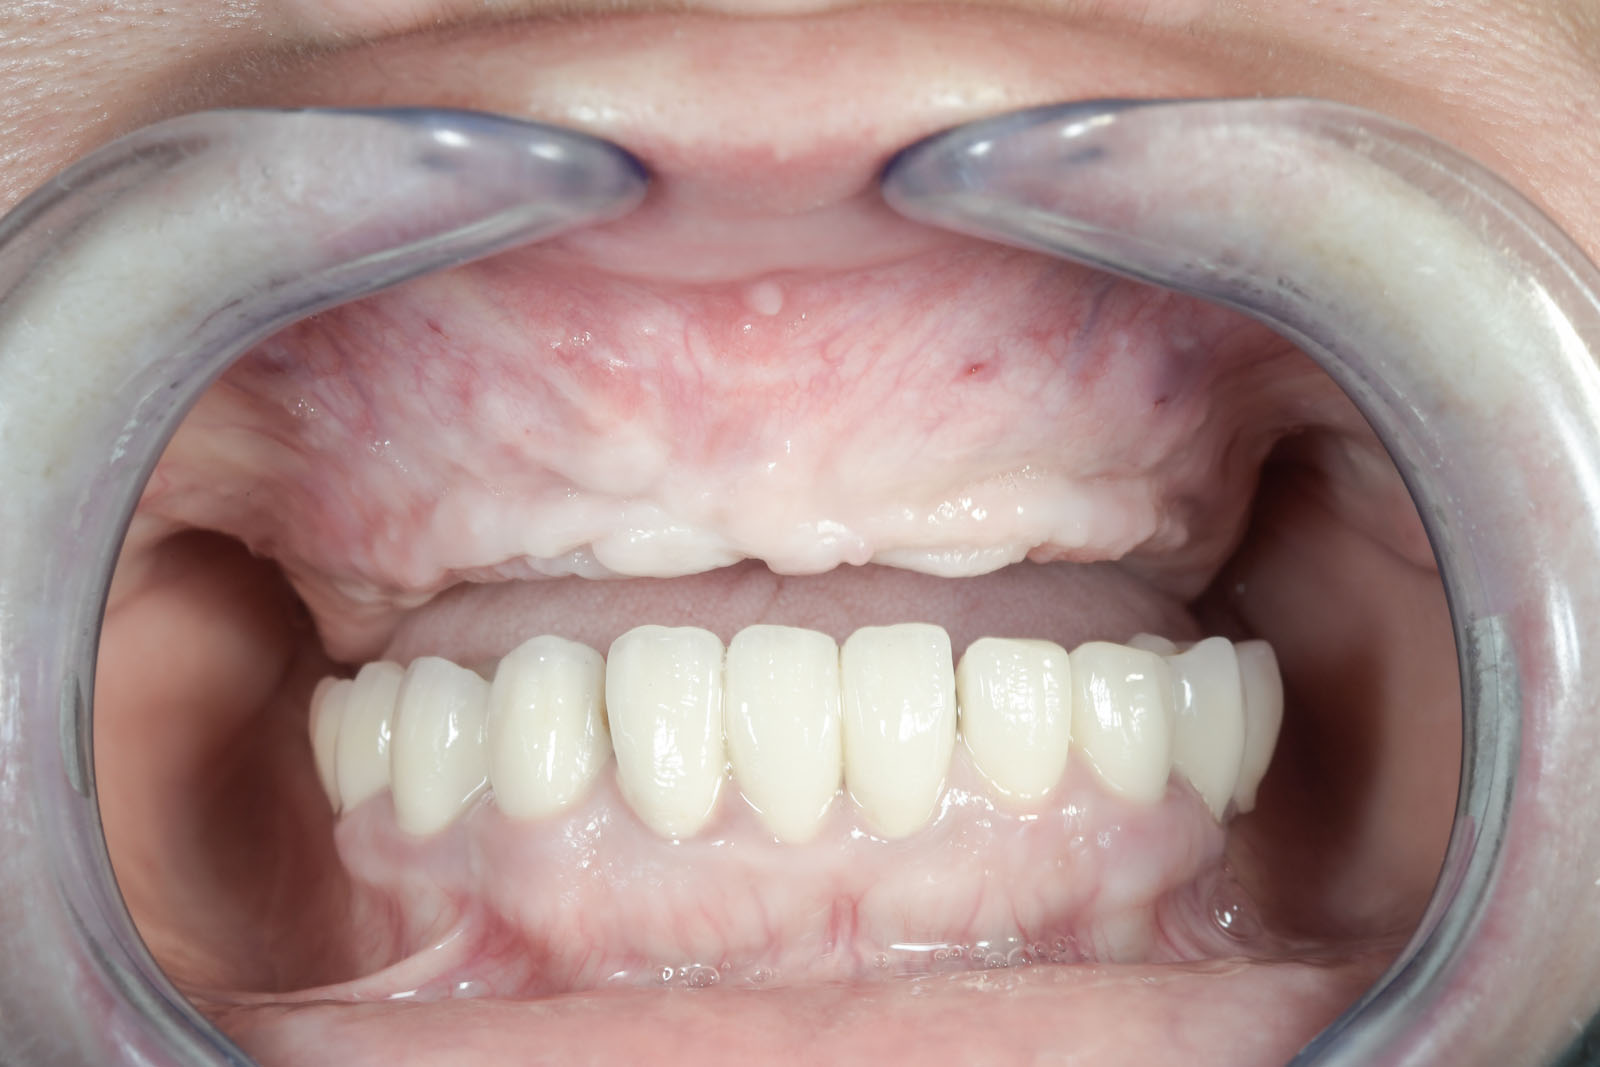

ROZWIĄZANIA PROTETYCZNE ALL-ON-4

Na implantach wszczepionych zgodnie z protokołem all-on-4 możliwe są do wykonania stabilne mosty, jak również ruchome protezy typu nakładowego. Uproszczenie i optymalizacja rozwiązań protetycznych możliwa jest dzięki zastosowaniu kątowych łączników typu MultiUnit (17°, 30°), które po przykręceniu do pochylonych implantów umożliwiają łatwe mocowanie mostu i obsługę serwisową pacjenta.

Przy bezzębiu zawsze istnieje możliwość wykonania uzupełnień protetycznych bez zastosowania implantów i są to całkowite protezy osiadające. W zależności od stanu kości szczęk i żuchwy można wykonać protezy lub mosty mocowane na implantach. Mocowanie protez na implantach może być rozłączne, jak w przypadku protez Overdenture, zwanych również nakładowymi. Oznacza to, że proteza w każdej chwili może być odczepiona od platform implantów przez pacjenta i wyjęta z jamy ustnej. Najbardziej jednak pożądane przez pacjentów rozwiązania protetyczne przy bezzębiu to stabilne, niezdejmowalne mosty, które cementuje się lub przykręca na stałe do implantów. One najlepiej imitują estetykę i funkcję naturalnego uzębienia.